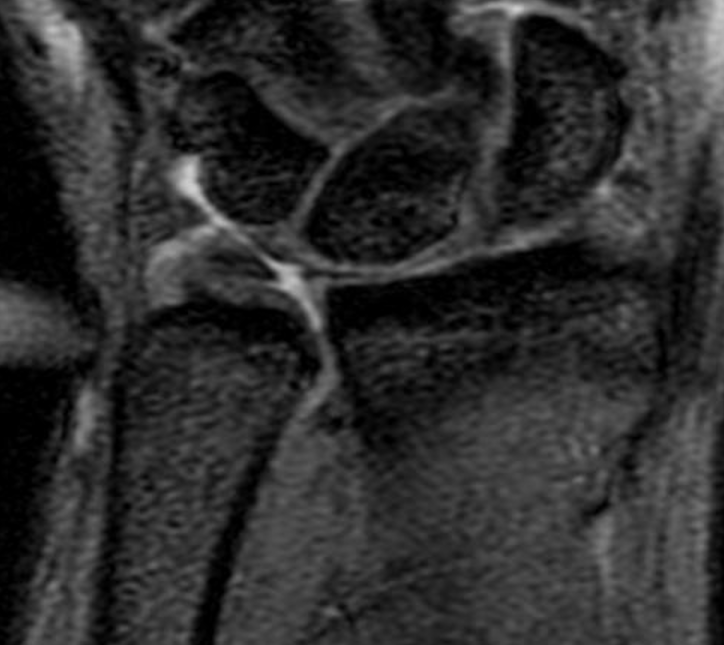

MRI

Normal

TFCC tears

Ulna sided tear

Radial sided TFCC tear

Central TFCC tear

Ulno-carpal abutment